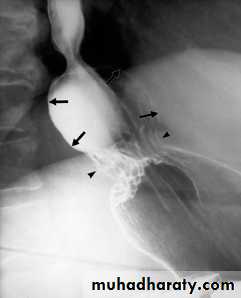

Volvulus

Frequently seen in sigmoid and less often in cecumThe twisted loop becomes greatly distended and proximal bowel dilatation is noted

The diagnosis can be made from plain film

Ba enema will show smooth tapered narrowing with marked dilatation of proximal bowel